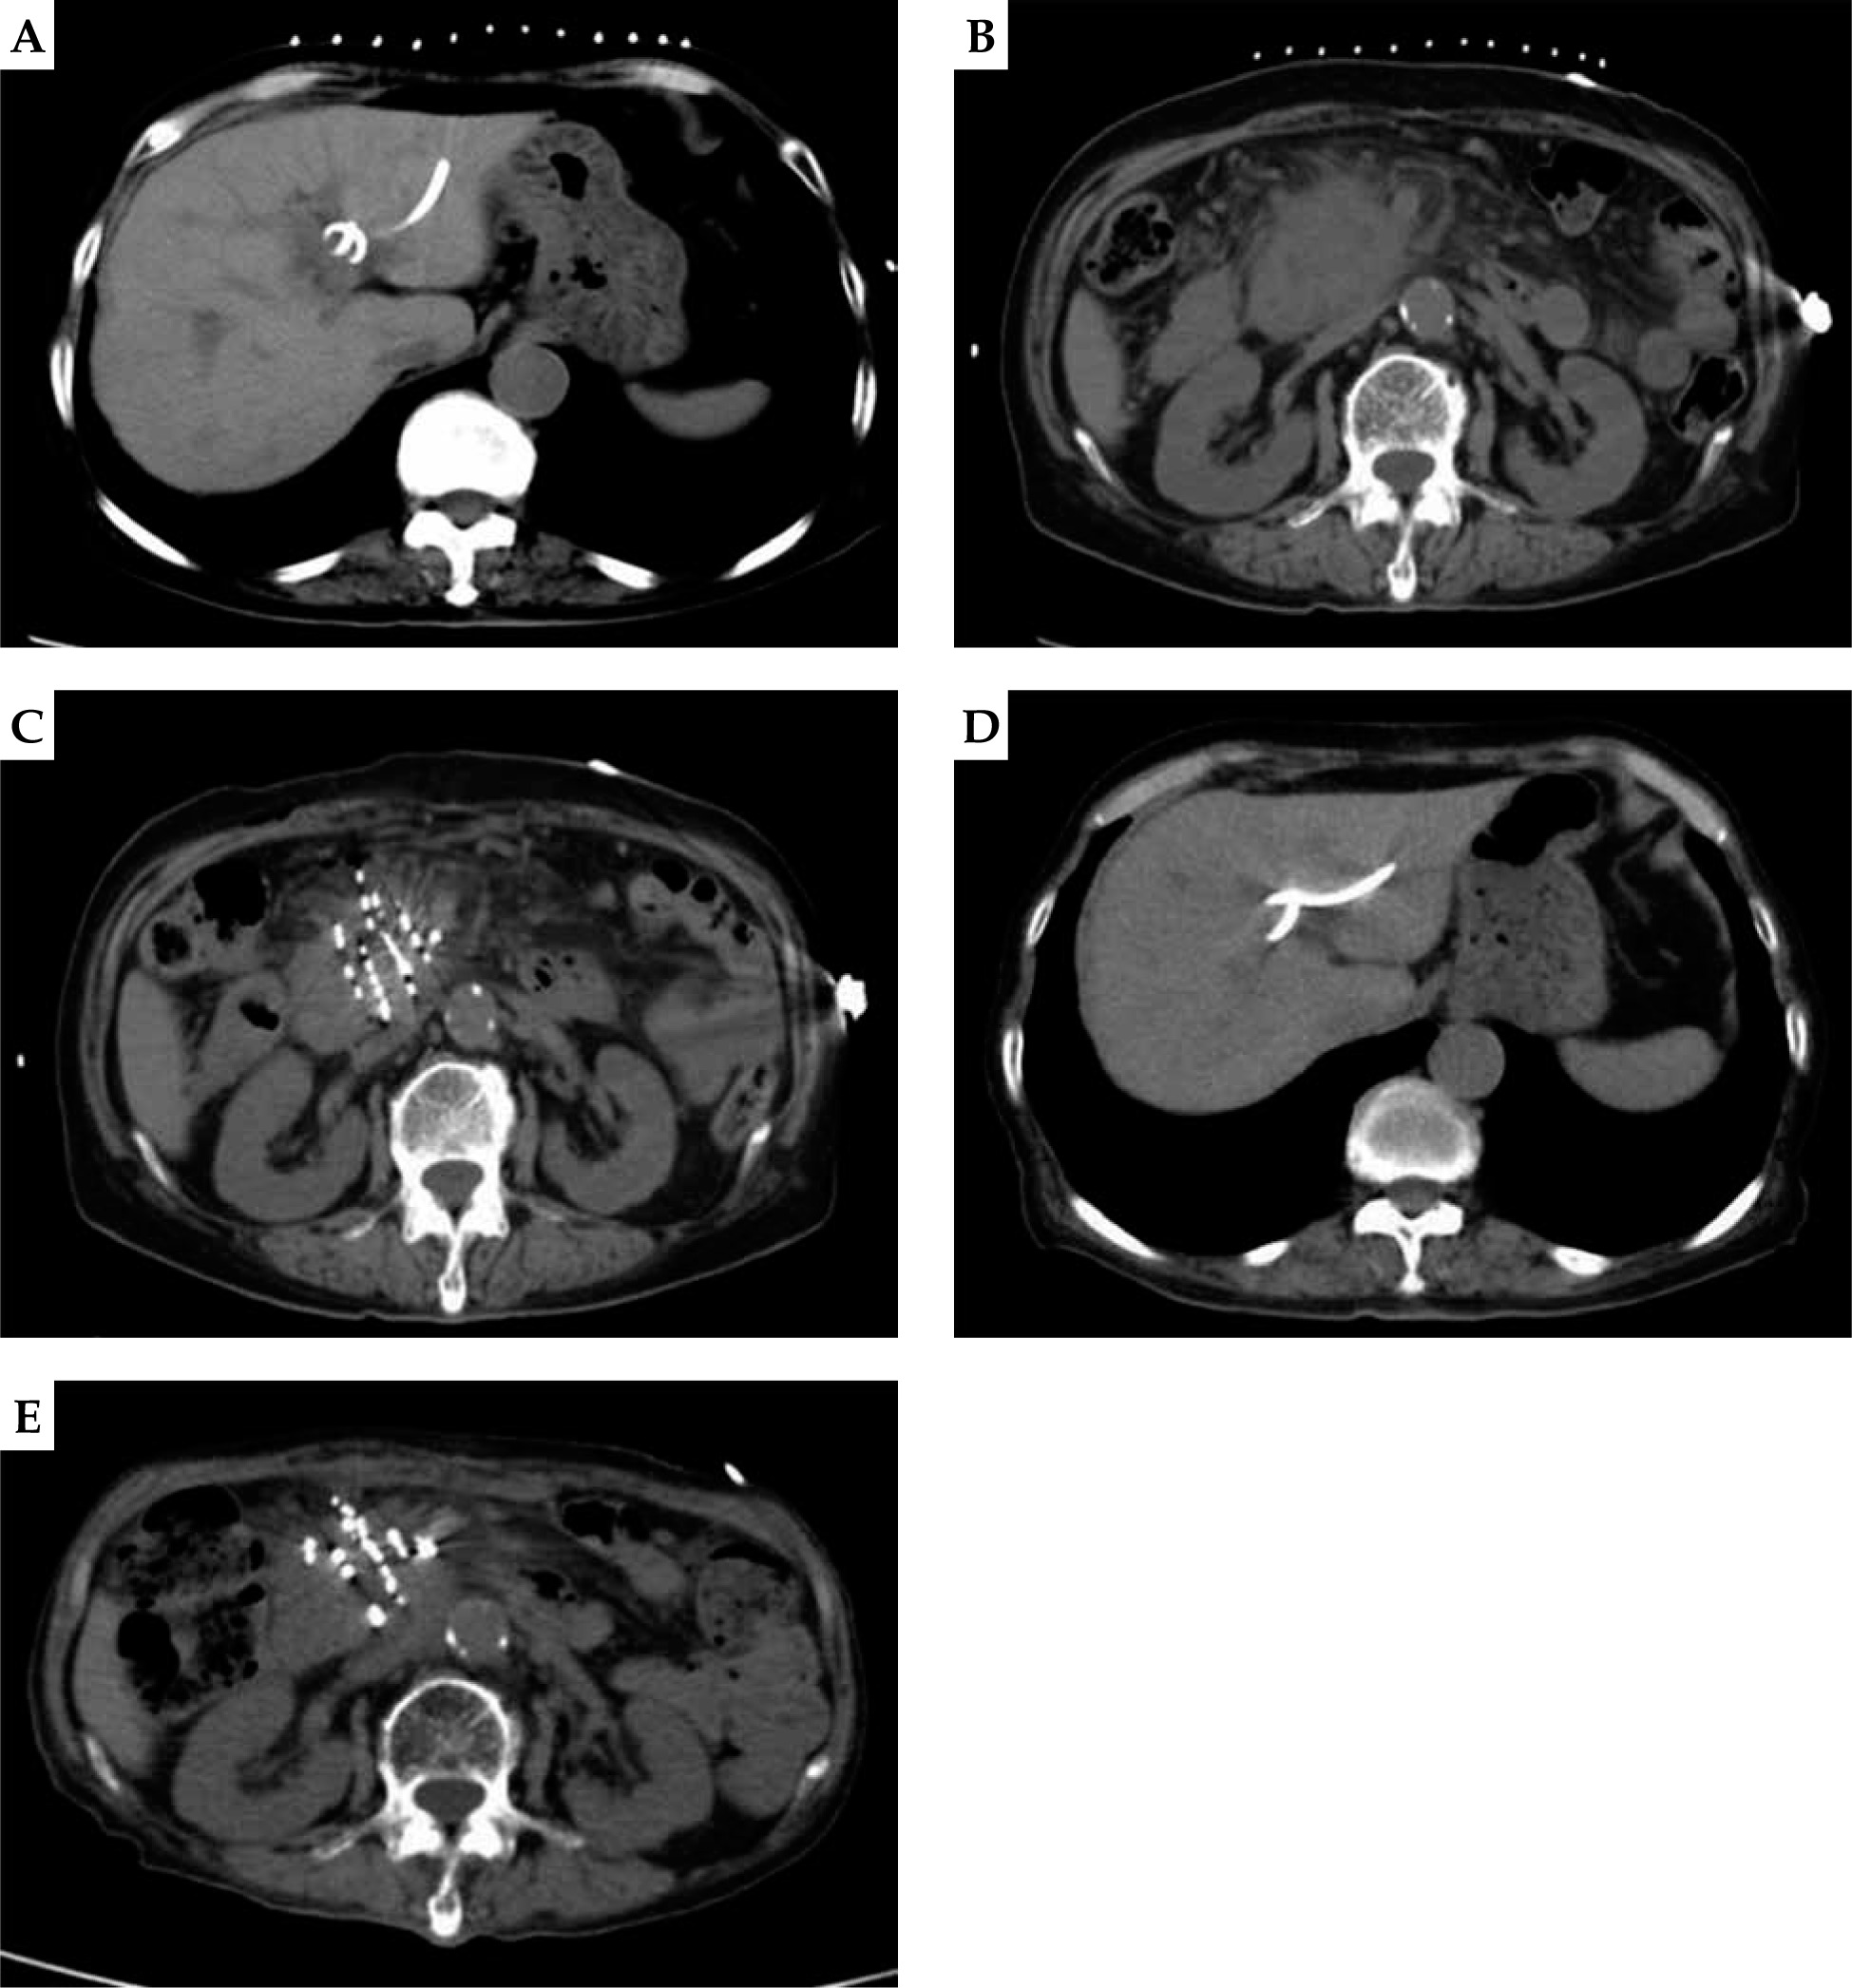

Fig. 1

A) A 73 years old female. Computed tomography (CT) scan shows CT-guided percutaneous transhepatic cholangial drainage (PTCD) in pancreatic head cancer complicated with obstructive jaundice. B) CT scan shows the maximum diameter of pancreatic head cancer of about 75.1 × 52.5 mm. C) CT scan shows CT-guided percutaneous radioactive seed implantation for pancreatic head carcinoma. D) CT scan shows the bile duct dilatation significantly improved after PTCD drainage. E) CT scan shows the lesions of pancreatic head cancer rechecked after 2 months of treatment, and the maximum diameter was about 47.7 × 38.9 mm. Evaluate partial response (PR)